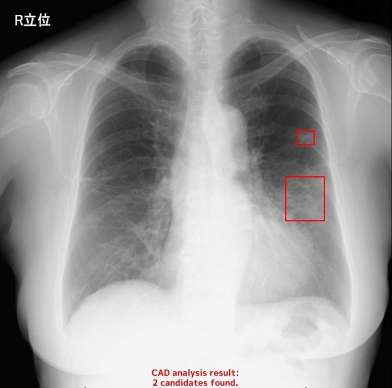

姶良市の大井病院は2月、AIを使った胸部エックス線検査の診断支援システムを使い始めた。エックス線画像をAIにかけると、1~2分後に肺がんが疑われる影を検出。大動脈の直径も自動的に計算する。

県内では、徳之島や沖永良部など離島を含む12医療機関が導入し、胸部エックス線や頭部MRAの検査で活用している。医師の偏在が進む中、AIを使った技術が医療の効率化や質の向上に役立つと期待される。同社の担当者は「医師の負担が増している中、診断の安心材料になれたら」と話した。